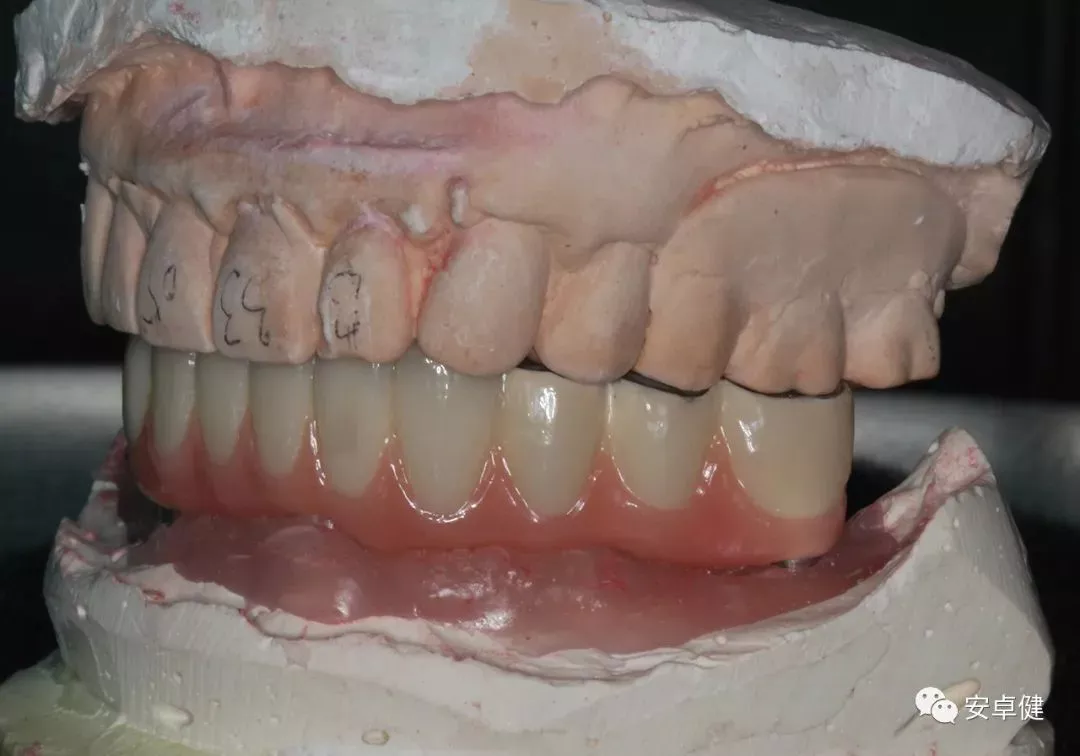

最终修复体蜡型合面照

• 制作最终修复体蜡型,分别于架及口内试戴检查其外形及咬合;

最终修复体蜡型上架正面观

最终修复体蜡型上侧面观